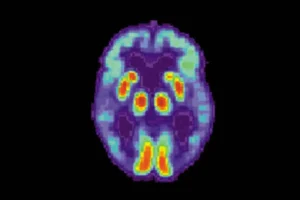

Исследовательская команда Института биоинженерии Каталонии совершила значимый шаг вперед в изучении природы болезни Альцгеймера, впервые детально разобрав, как именно начинается формирование амилоидных бляшек в мозге. Эти скопления считаются главным маркером заболевания и напрямую связаны с разрушением когнитивных функций. Основное внимание ученые уделили изменениям структуры пептида Aβ42 — ключевого элемента в прогрессировании патологии.

Авторы работы провели масштабный анализ — были рассмотрены более 140 тысяч вариантов пептида Aβ42, который относится к семейству бета-амилоидов. Именно из этого белка формируются те самые амилоидные фибриллы, которые постепенно скапливаются в мозге, образуя токсические бляшки. Эти структуры оказываются определяющими в развитии самых тяжелых форм нейродегенеративных заболеваний, а особенно — болезни Альцгеймера.

Научной команде удалось составить обширную энергетическую карту агрегации амилоидного пептида. Благодаря этому теперь возможно проследить, какие именно мутации оказывают наибольшее влияние на риск формирования опасных фибрилл. Установлено, что решающее значение принадлежит C-концевому гидрофобному участку пептида — именно здесь стартует процесс образования фибриллярных структур. Контакт и взаимодействие белка в этой зоне запускает весь патологический каскад.

Составленная энергетическая карта стала первым в своем роде детальным описанием того, как разнообразные изменения в структуре пептида влияют на его склонность к агрегации в переходном состоянии. Специалисты уверены, что предотвращение этого перехода — ключ к созданию инновационных методов лечения и профилактики заболевания.